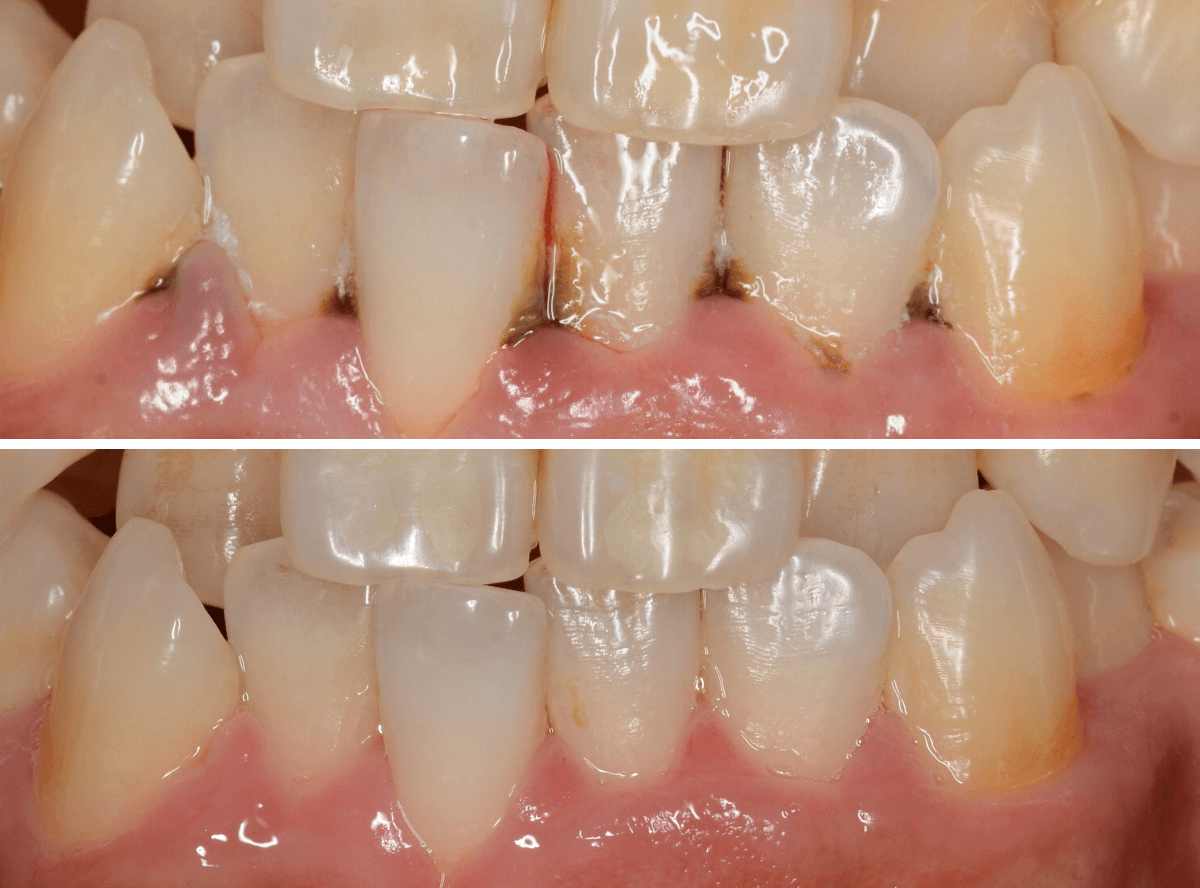

Case.2

今回は、上の前歯の縁下歯石の除去をしたお話です。

写真の左の矢印の歯肉が退縮して腫れています。

右の矢印の歯肉と比べてみるとわかると思います。

こういった歯肉の形をしている部分は、歯石がたまっていることが多いです。

拡大してみると、縁下歯石(歯肉の中に入り込んだ歯石:歯肉に大きく悪影響を与えます)が顔を出しているのがわかります。

かなり歯肉の中に歯石が入り込んでしまっていると思われます。

歯肉の中の歯石は歯にべっとりとこびりつきますので、除去するには麻酔をして引きはがす処置が必要です。

歯石除去後、約1週間です。

歯肉がひきしまってきたのがわかるでしょうか。

治療前との比較です。

比べると、違いがわかると思います。

まだ若い患者さんで本格的な歯周病に進行する前ですので、歯ブラシの徹底によって、もっと歯肉が改善されるのも期待できます。

逆に、歯周病が本格的に進行してしまうと、歯石除去をしても歯肉や歯の周りの骨は完全には元には戻りません(><)

その後、この患者さんは熱心に通院とお手入れをされて、約二か月が経ちました。

歯肉は順調に引き締まってきました。

歯周治療は、ご本人のメンテナンスなしには結果が出ません、頑張ってらっしゃる形が見えて、とても嬉しいですね

こちらが比較写真です。

並べてみると、治り具合がよりわかりますね